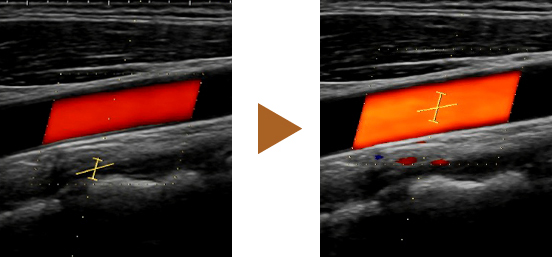

Los ajustes como la posición de la región de interés de color y el cursor se pueden configurar con un solo clic en el examen Doppler de un vaso. También se admiten transductores convexos. Además, el IMT automático puede medir automáticamente el grosor íntima-media (Intima-Media Thickness, IMT).

iVascular puede ajustar los parámetros como la posición de la región de interés de color y la posición/tamaño/ángulo de la puerta de muestra con un solo clic de un botón en un examen Doppler de un vaso.

Debido a que esta función también está disponible en la pantalla del trapezoide, se puede esperar que acorte el tiempo de examen no solo para una arteria carótida, sino también para un vaso de la extremidad inferior.

Reducción del 35 % en el tiempo empleado para los exámenes de los vasos de las extremidades inferiores (aproximación en comparación con los sistemas convencionales).